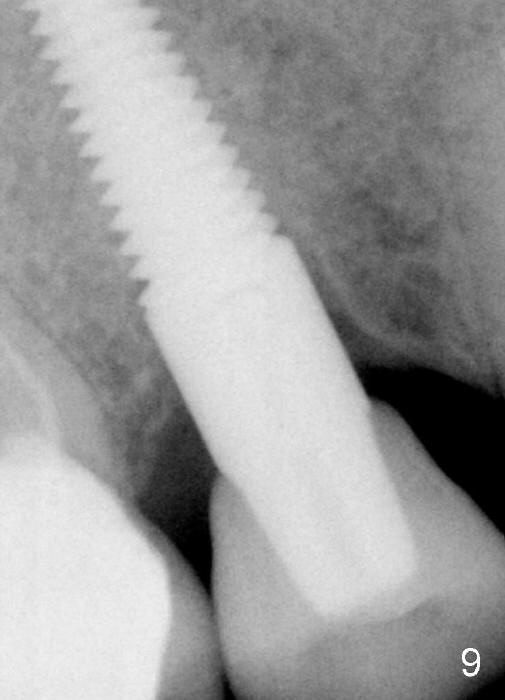

Fig.9: Nineteen months post cementation. The newly forming mesial lamina dura is thicker and closer to the implant, as compared that in Fig.7.  Or the difference is probably due to different angulation when X-ray is taken.  Follow up is necessary.